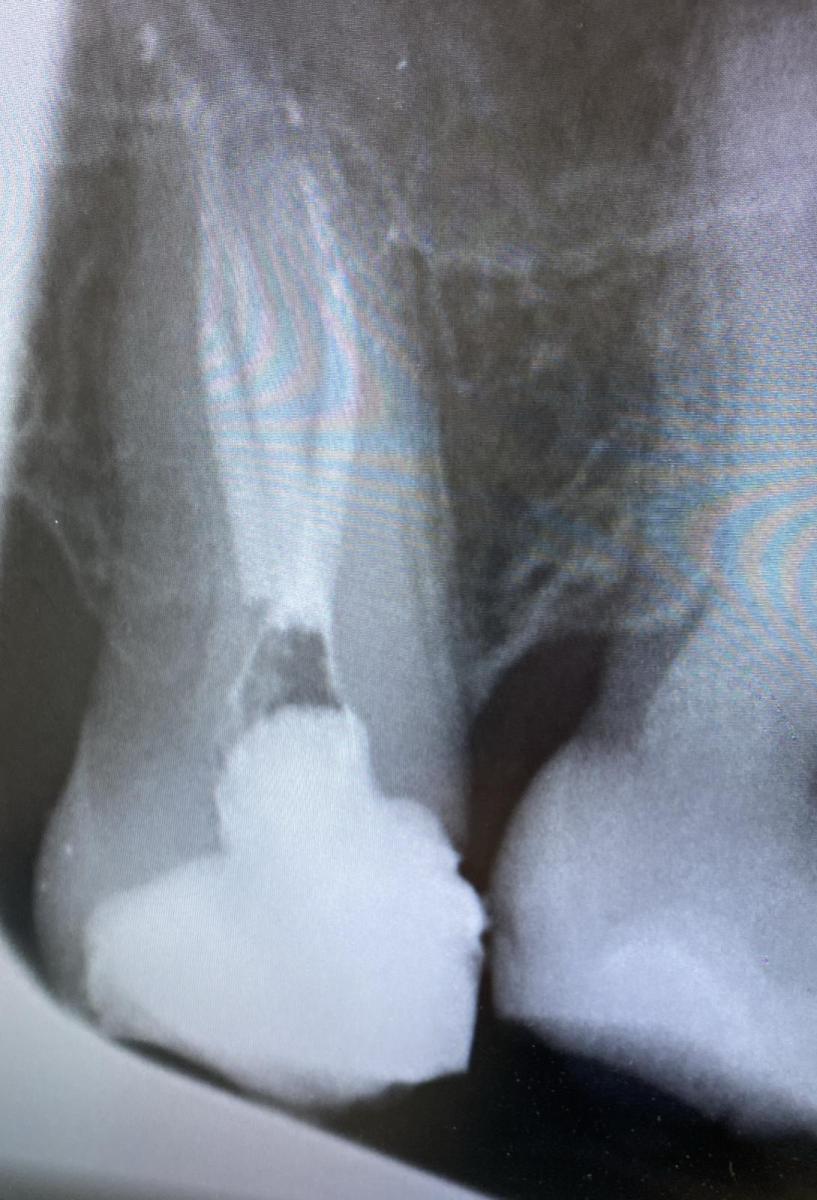

Спасибо Вам. Добовляю снимки до и после.

в 8 на момент снимка оставили временную пломбу. Сказали поменяют через неделю на постоянную. 7 зуб пока не трогали. Сказали 99% каналы чистить.

Вторую 8 врач сказала нет смысла сохранять даже если я готова на лечение каналов и огромную для таких зубов цену.

Удалили. Рентген не делали сказали в этом нет никакого смысла ( я надеялась что посмотрят и решат всё таки лечить).

Головой понимаю что зуб просто ужасный, правда не было смысла лечить? Это верхняя 8. На той стороне к сожалению в низу после травмы нет и 7 и 8 зуба (на имплант не созрела ещё) и верхняя 7 конечно немного ушла в низ.